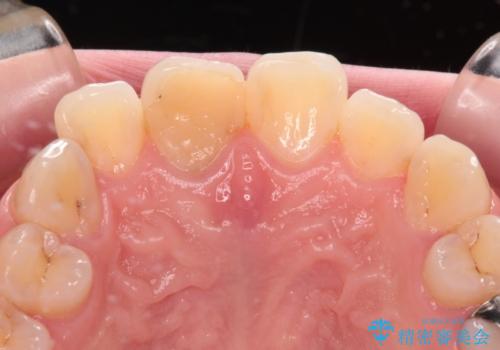

- 事故でぶつけて神経を取り除いた歯が変色したとのことで来院された患者様です。

処置直後は欠けた部分を詰めた材料で見た目に問題なかったそうですが、年々変色してきて、かなり目立つようになっていました。

根管治療された状態に大きな問題はなかったため、土台を植立し、オールセラミッククラウンにて補綴治療を行うこととしました。